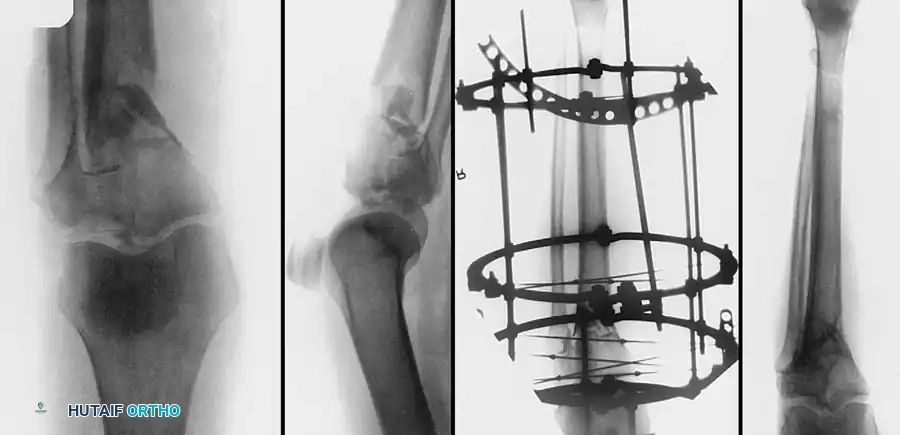

التقييم المبدئي والتحكم في الأضرار

في الإصابات عالية الطاقة التي يصاحبها تورم شديد أو فقاعات جلدية، فإن إجراء جراحة مفتوحة فورية يحمل خطرا كبيرا لحدوث تلوث وعدم التئام الجروح. لذلك، يطبق الأطباء مبدأ جراحة التحكم في الأضرار.

استخدام المثبت الخارجي المؤقت للركبة

يتم تركيب مثبت خارجي يمتد عبر الركبة كإجراء مؤقت. يعمل هذا المثبت على إعادة طول الساق واستقامتها، ويسمح للأنسجة الرخوة والجلد بالتعافي لمدة تتراوح بين أسبوعين إلى ثلاثة أسابيع قبل إجراء الجراحة النهائية.

تثبيت الكسر باستخدام الشرائح والمسامير

في الكسور المعقدة التي تشمل جانبي الركبة، غالبا ما يتطلب الأمر استخدام شريحتين معدنيتين لضمان عدم انهيار العظم تحت تأثير وزن الجسم.

استخدام شريحتين لتثبيت الكسور المعقدة

يقوم الجراح باستخدام جهاز الأشعة التداخلية للتأكد من استعادة المحور الميكانيكي للساق، والتأكد من عدم اختراق أي مسامير لسطح المفصل.

التصوير الإشعاعي أثناء الجراحة للتأكد من التثبيت

متابعة التئام الكسر بالأشعة بعد الجراحة

مراحل متقدمة من التئام كسر هضبة التيبيا